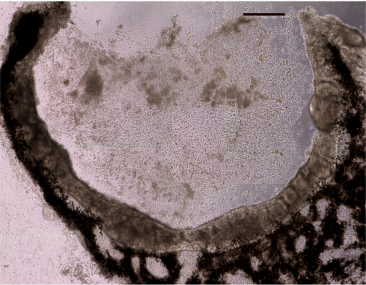

In this study, state of the art sequencing technologies were used to identify disease-causing mutations in the USH2A gene in an adult patient with autosomal recessive Retinitis Pigmentosa. Induced pluripotent stem cells (iPSCs), generated from the patient's skin, were differentiated into multi-layer eyecup-like structures with features of human retinal cells. The inner layer of the eyecups contained immature photoreceptor cells that expressed photoreceptor markers and exhibited cilia and basal bodies characteristic of outer segments. Analysis of the USH2A transcripts of these cells revealed that one of the patient's mutations causes a large piece of intron 40 to get transcribed into RNA, which induces a translation frameshift and a premature stop codon. Western blotting revealed an upregulation of proteins (GRP78 and GRP94) associated with mutation induced stress of the endoplasmic reticulum. This suggested that the patient's other USH2A variant (Arg4192His) causes disease through protein misfolding. Transplantation into 4-day-old immunodeficient retinal degenerative mice resulted in the formation of morphologically and immunohistochemically recognizable photoreceptor cells suggesting that the mutations in this patient act via post-developmental photoreceptor degeneration/death.